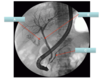

Label A-C in this endoscopic retrograde cholangiopancreatography (ERCP)

A: cystic duct

B: hepatic duct

C: pancreatic duct